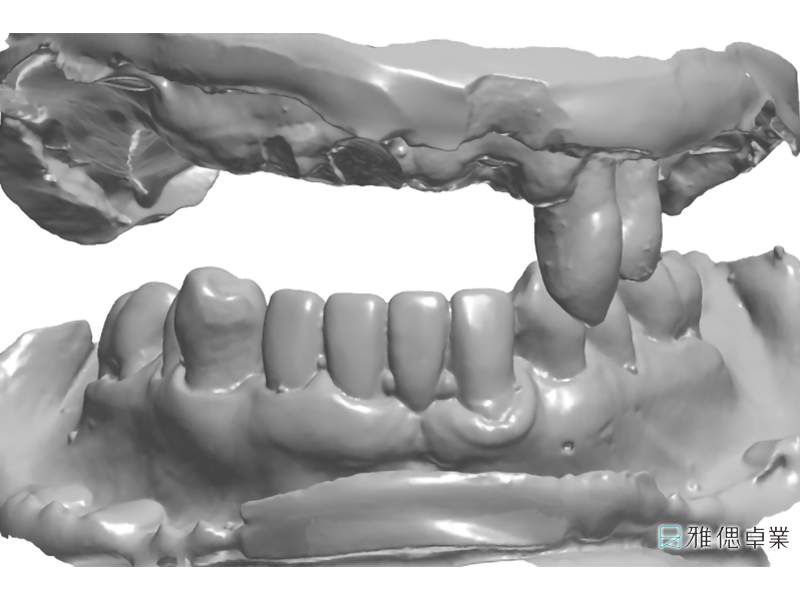

原始診斷模型

數位軟體設計假牙基座